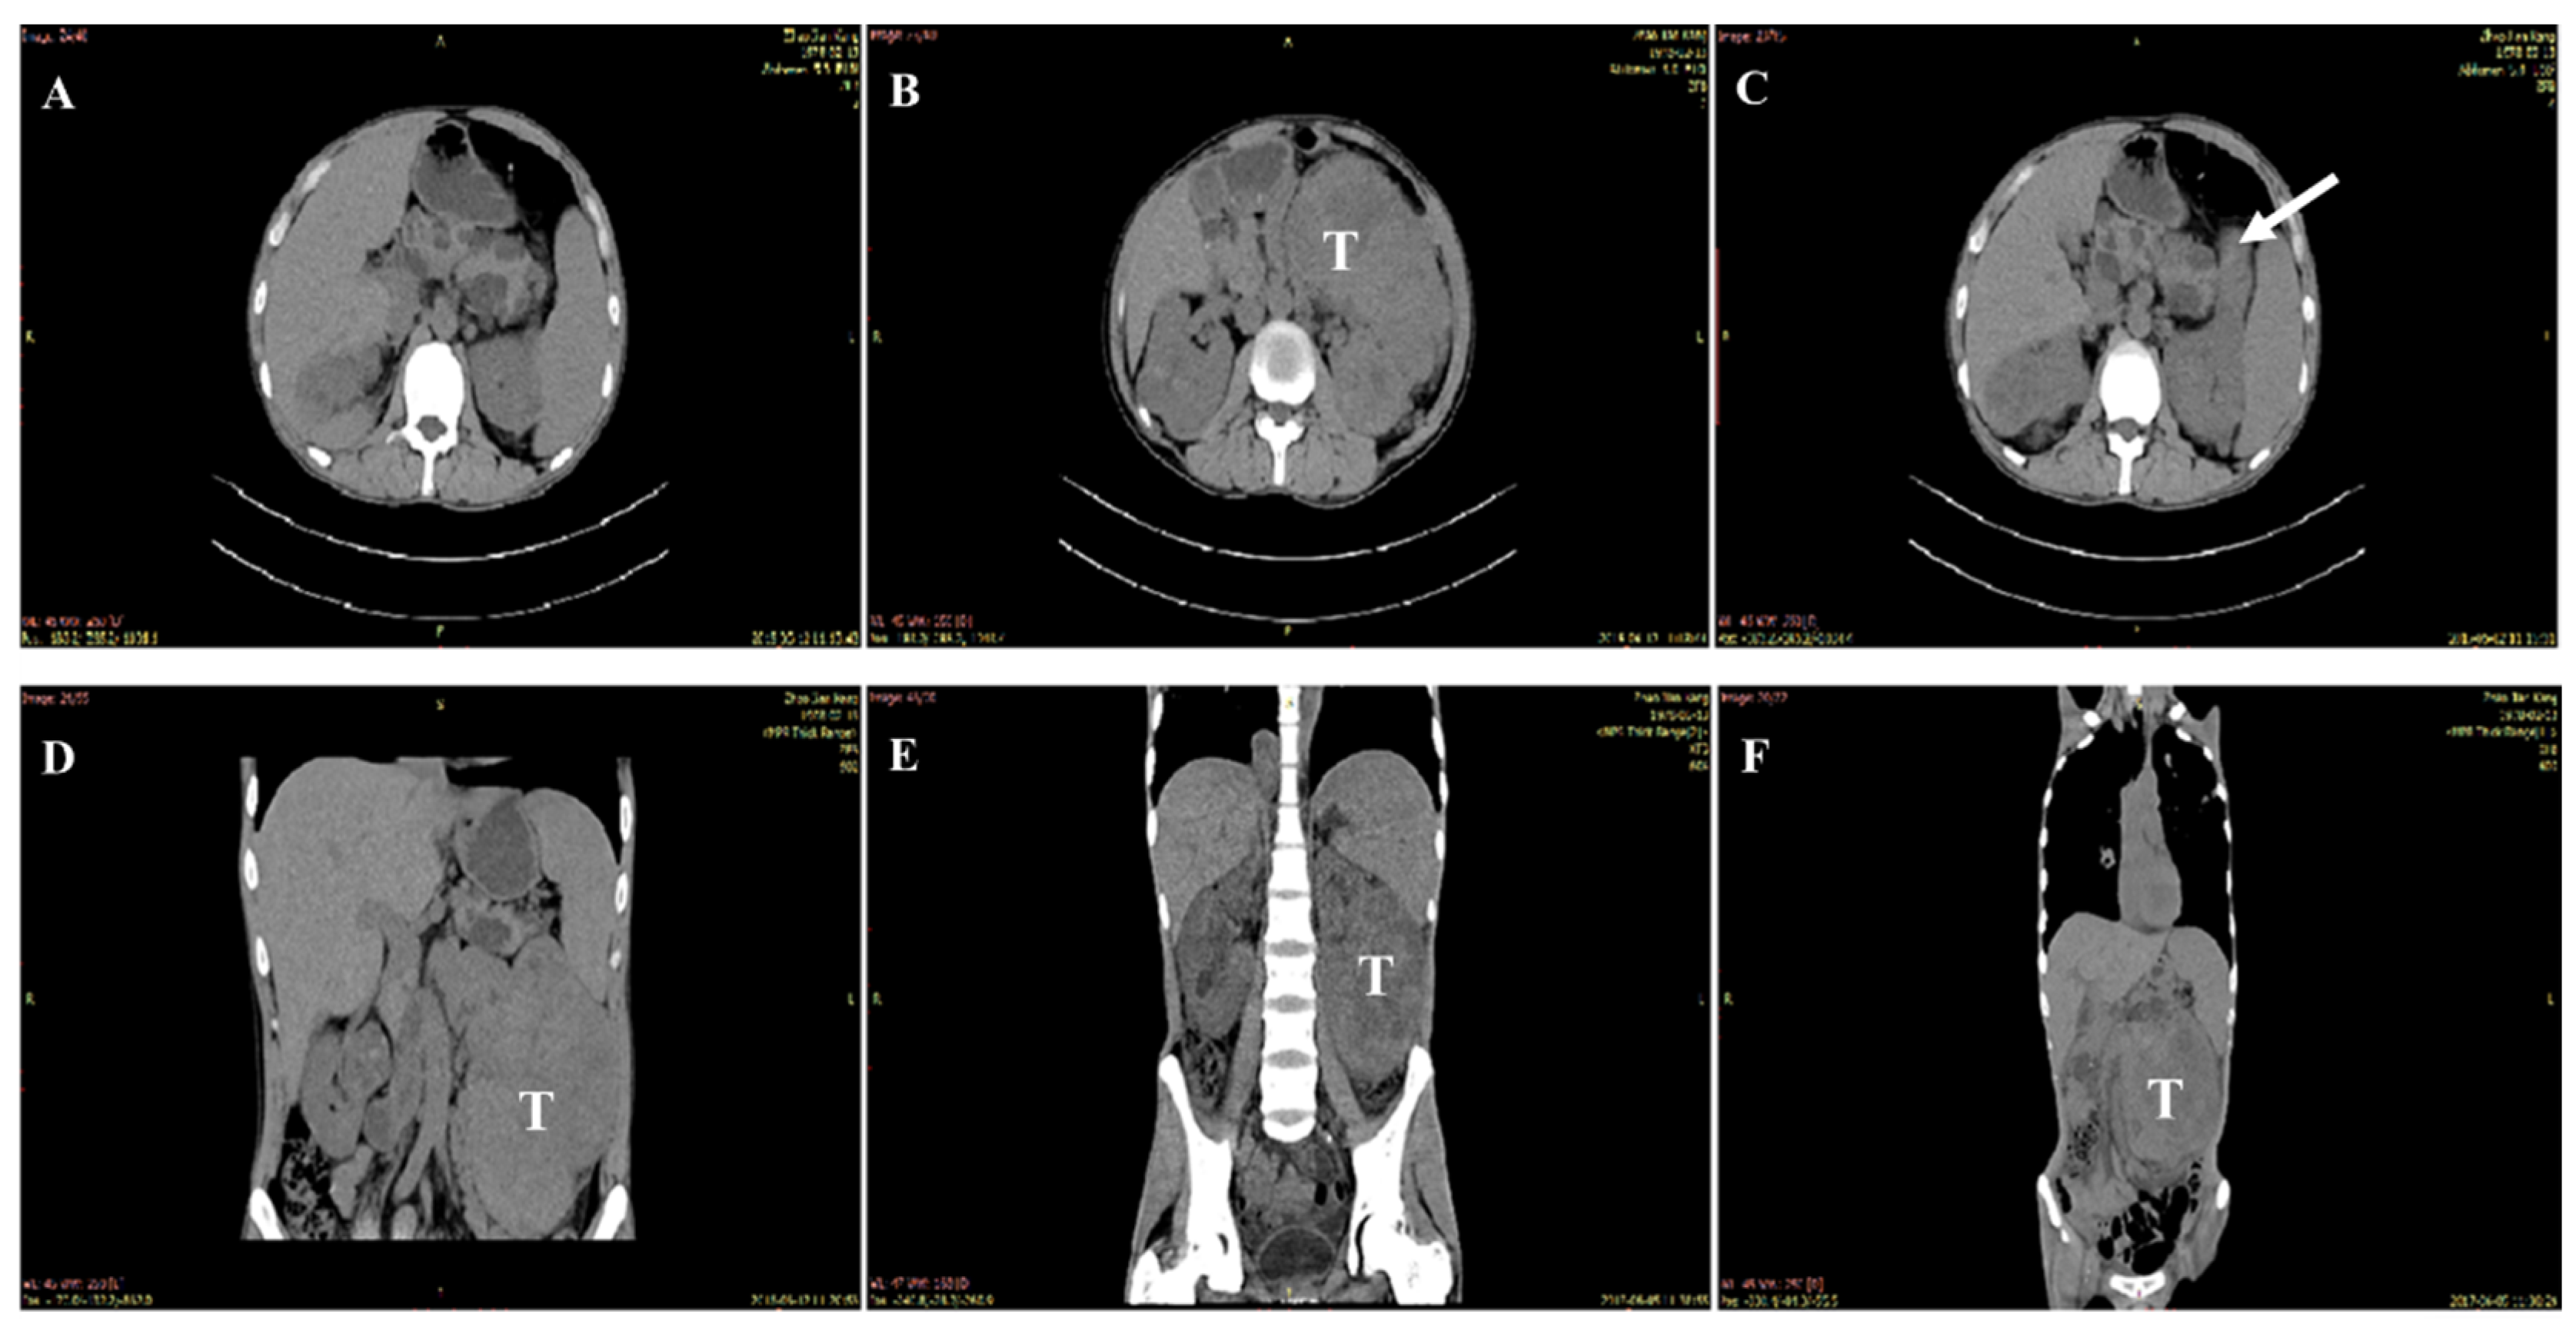

3.1. Clinical Findings